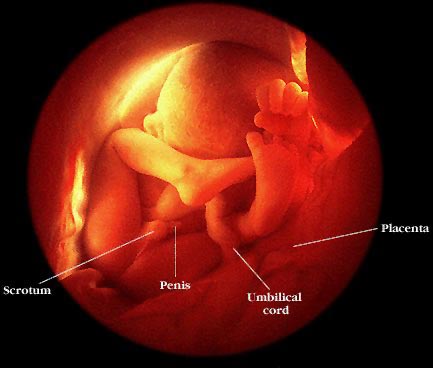

Vika 32

Heilinn heldur áfram hröðum þroska. Húðin breytist talsvert og verður barnið nú feitara en áður og svonefnd barnafita sest á það. Dúnmjúku hárin sem umluku barnið meðan húðin var að þroskast fara að hverfa. Bein halda áfram að styrkjast og vaxa og krefst sá þroski mikils magns af kalsíum. Barnið er hér 1,9 kg að þyngd og 40,5 cm að lengd.